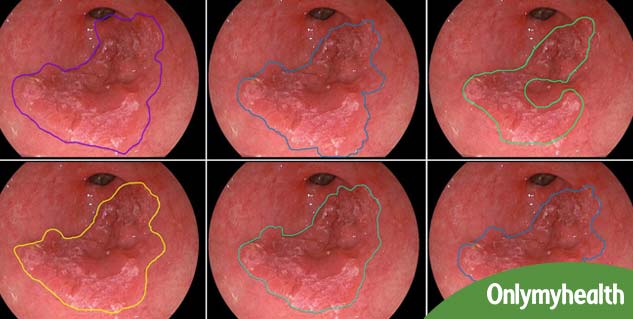

पेट में जलन और खट्टी डकारों को हम अक्सर सामान्य परेशानी समझ लेते हैं। लेकिन, यह समस्या अगर नियमित हो और इसके साथ अन्य लक्षण भी नजर आयें तो आपको ग्रासनली का कैंसर भी हो सकता है। एसोफेगल कैंसर, एसोफेगस में कोशिकाओं की असामान्य बढ़ोत्तरी होती है। एसोफेगस गले से आपके पेट तक भोजन और पानी ले जाने वाली नली को कहते हैं। एसोफेगस जहां पर पेट से जुड़ती है वहां इसकी परत एक अलग प्रकार की कोशिकीय बनावट की होती है, जिसमें विभिन्न केमिकल्स का रिसाव करने वाली अनेक ग्रंथियां या संरचनाएं होती हैं। यदि एसोफेगस का कैंसर उस हिस्से से शुरू होता है जहां पर ट्यूब पेट से मिलता है, तो इस कैंसर को स्क्वामस सेल कार्सिनोमा कहते हैं। यदि यह एसोफेगस के ग्रंथियों वाले हिस्से से शुरू होता है तो इसे एडेनोकार्सिनोमा (ग्रंथियों की बनावट वाले हिस्सें का कैंसर) कहते हैं।

एसोफैगल कैंसर के लक्षण